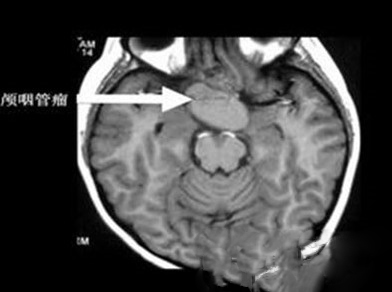

4、隐藏在脑中的牙齿

一个出生于马里兰州的4个月大婴儿可能是世界上第一个在脑子里长牙齿的人,据悉这一情况是由于罕见的脑瘤导致的。

医生最初因为发现该婴儿的脑部成长速度明显超过同龄的孩子而开始怀疑其脑部是否有一些问题。通过脑补扫描,医生发现该婴儿的脑袋里有一个肿瘤,而其中还长有一个类似牙齿一样的东西。

目前该婴儿脑中的肿瘤已被移除,而该婴儿也逐渐恢复了健康。